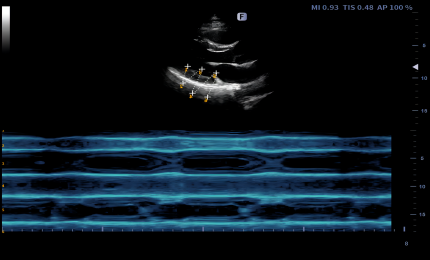

Curved AM

Curved Anatomical M-Mode (CAM) technology can show all the spatial and temporal relationship of myocardial segment movements during the cardiac cycle in the scanning sector, which provides a new measurement method to quantitatively analyze the abnormalities of segmental myocardial motion during systolic or diastolic period.